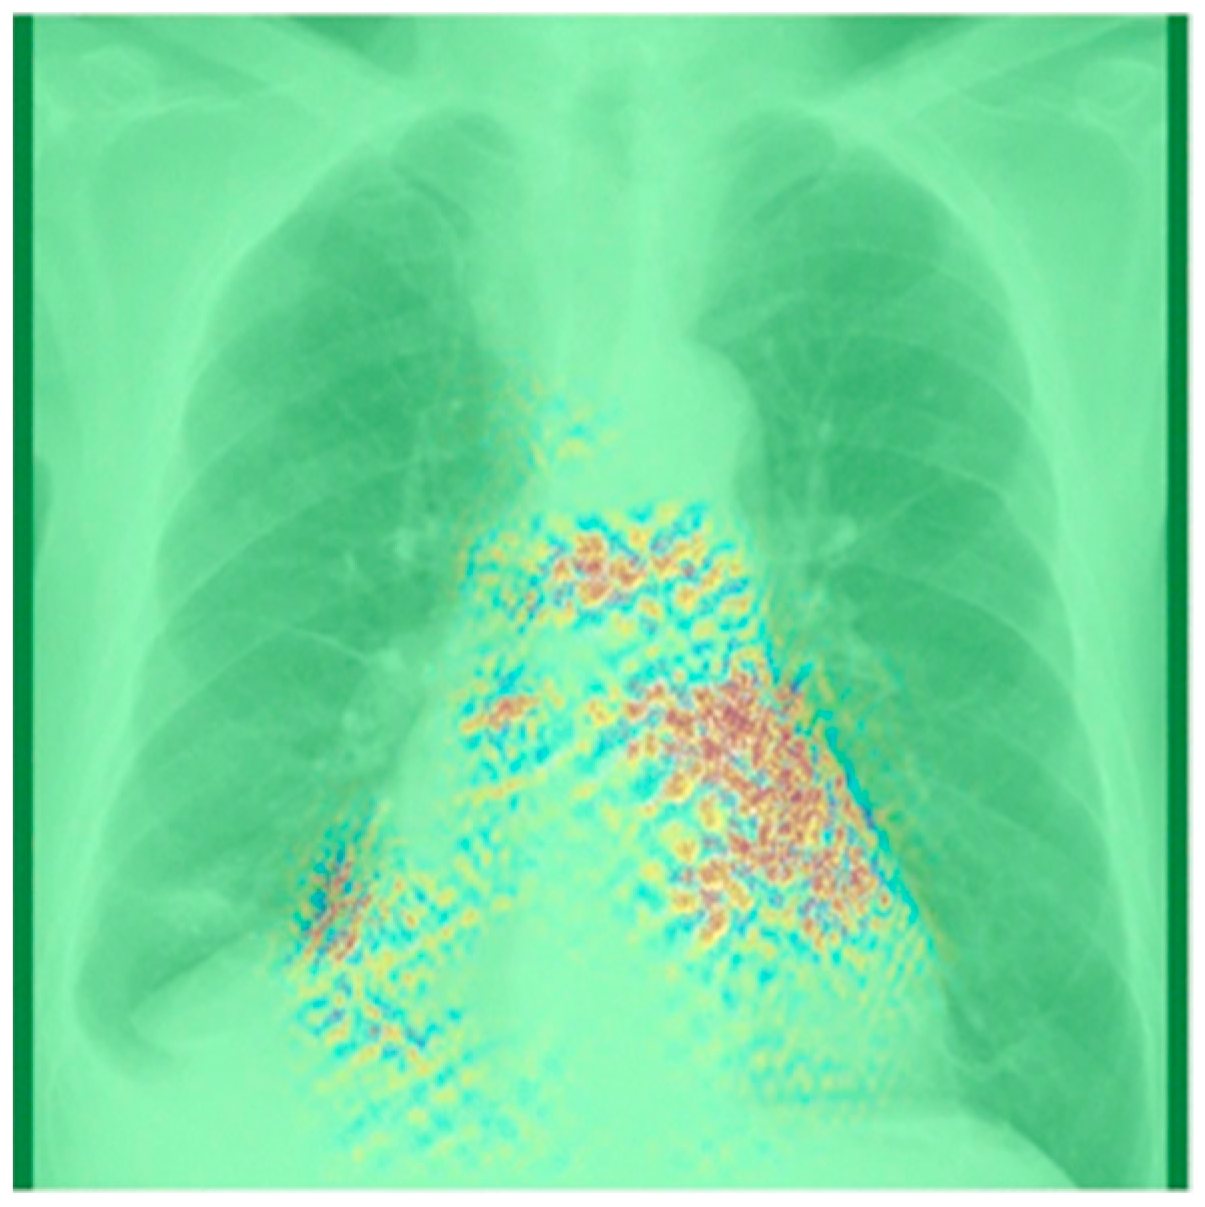

To enhance the explainability of models, visualization techniques such as Grad-CAM [92] can be employed. Grad-CAM generates a heatmap that highlights the regions that the model focuses on during its decision-making process using the gradients of the target concept, such as the subtle anatomical remodeling associated with AF. Liu et al. [51] used Grad-CAM visualization and identified hotspots in the PVs and the atria. These findings are consistent with clinical observations and imply that the DL model learned features related to the shape and size of the PVs and atria. Similarly, Matsumoto et al. [55] applied Grad-CAM visualization to the true positive predictions, resulting in the regions of interest primarily located in the upper left region of the cardiac shadow, as shown in Figure 8. While Grad-CAM visualization provides a rough visualization of significant regions, it may not be adequate for patients with AF who do not exhibit clear anatomical abnormalities. Hence, more robust methods for explainability, such as the use of DL to efficiently extract interpretable features for classification [106], are required to increase confidence in the diagnosis and prognosis of AF.

Figure 8.

A composite Grad-CAM and guided backpropagation image superimposed on a chest radiograph. The primary region of interest is located in the upper left section of the heart shadow, consistent with the left atrium region. Using Grad-CAM visualization method improves the explainability of the output of deep-learning-based classification model. Figure source: [55].